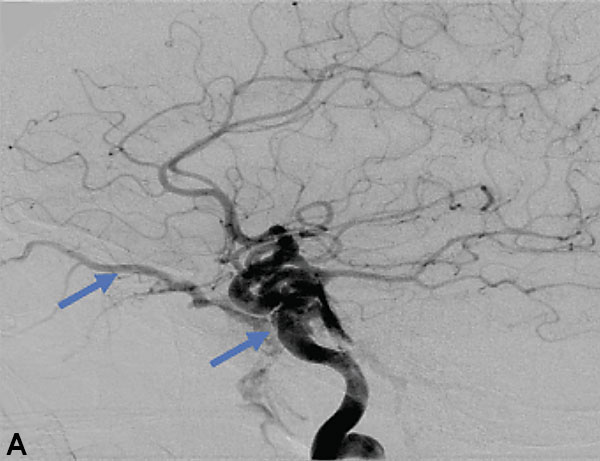

Collateral venous drainage into the orbit and skull base was observed (Figure A). After successful cannulation of the direct aperture between the right carotid artery and the cavernous sinus, balloon-assisted coil embolization of the posterolateral compartment was performed until the fistula was closed (Figure B and C). He experienced immediate cessation of his pulsatile tinnitus with an early improvement of the right VI nerve palsy and near-complete recovery of his vision within 6 weeks

Figure: (A) Right ICA Cavernous Fistula with Venous Shunting (B) Balloon Assisted Coil Embolization (C) Fistula Cured Post Embolization